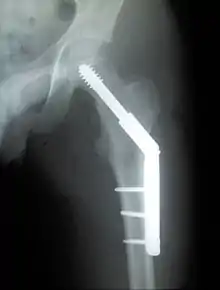

Dynamic hip screw

Dynamic hip screw (DHS) or Sliding Screw Fixation is a type of orthopaedic implant designed for fixation of certain types of hip fractures which allows controlled dynamic sliding of the femoral head component along the construct. It is the most commonly used implant for extracapsular fractures of the hip,[1] which are common in older osteoporotic patients. There are 3 components of a dynamic hip screw, including a lag screw (inserted into the neck of the femur), a sideplate and several cortical screws (fixated into the proximal femoral shaft). The idea behind the dynamic compression is that the femoral head component is allowed to move along one plane; since bone responds to dynamic stresses, the native femur may undergo primary healing: cells join along boundaries, resulting in a robust joint requiring no remodeling.